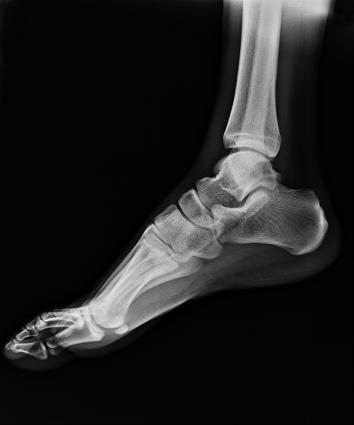

電動旋轉內(nèi)平衡結構,可實現(xiàn)快捷擺位,滿足特殊體位的靜態(tài)與動態(tài)檢查。

滿足不同身高的受檢者快速地進行胸片的靜態(tài)及動態(tài)檢查,適合大規(guī)模體檢。

SID可拉伸至1.8米,滿足標準胸片、職業(yè)性塵肺病檢查等特殊需求。